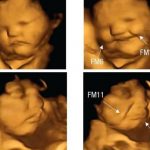

¡Uyy que tierno! Reacción de los fetos según lo que coma su «mamita»

¿Sabías que los bebés en el vientre de su madre reaccionan de forma diferente a los sabores y olores? Pues déjanos decirte que si,...